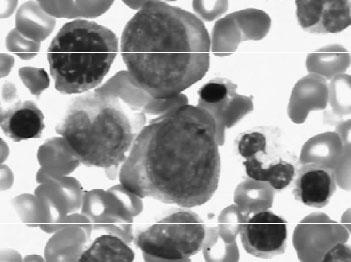

1976年法、英、美三国制订了FAB分型诊断标准,1985年以后又有多次小的修正。目前FAB的分型诊断标准已为世界各国广泛应用,虽然近年世界卫生组织(WHO)提出了新的分型诊断标准,目前已逐渐被广泛采用(见图3—1、图3—2、图3—3),现介绍FAB分型诊断标准要点如下。

图3—1 ALL—L骨髓象

图3—2 ALL—L骨髓象

图3—3 ALL—L骨髓象